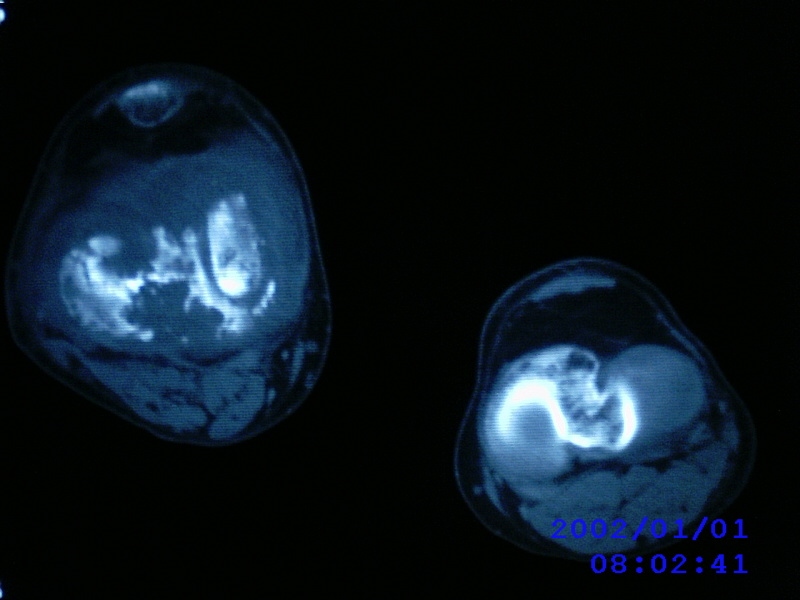

患者,男性,57岁,右侧膝关节疼痛伴肿脹10余年,加重一个月。

关节积液,关节间隙变窄,边缘骨破坏。考虑膝关节tb

关节积液,关节间隙变窄,骨质疏松,多发骨破坏,边缘轻度硬化,近端胫腓骨髓腔软组织充填,患者病史较长,支持考虑结核

有皮质的破坏~有死骨存在

结合临床表现,考虑结核。。。。课医照个胸片

多发骨破坏,骨质疏松,关节积液。考虑右膝关节结核。